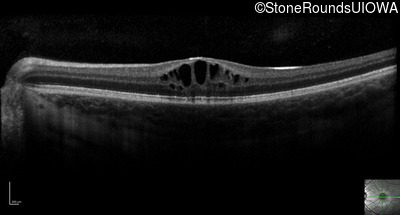

Optical Coherence Tomography - Left - 20/40 +2

Exemplar / OCT Stack